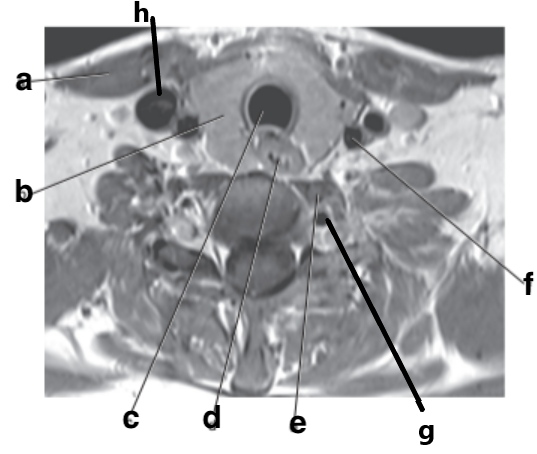

What is letter a?

Vertebral artery

What is letter b?

Radial head

What is letter c?

Trachea

What is letter f?

Cervical Spinal cord

Basilar artery